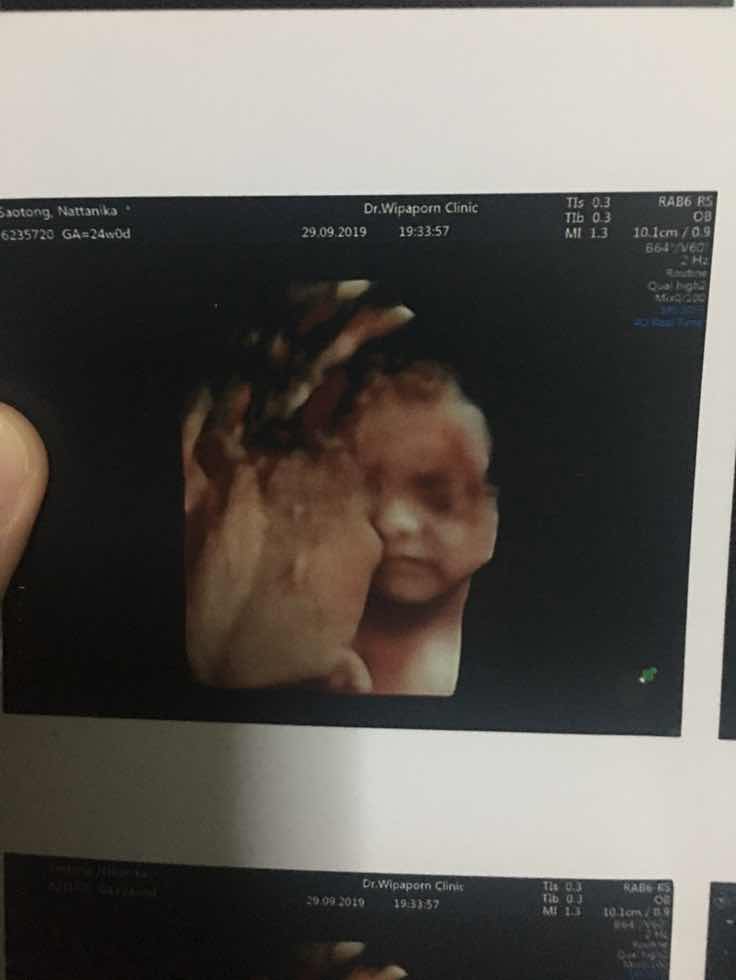

บ้านนี้มุดแอบค่ะ